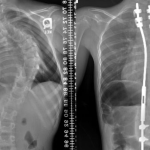

Kırıklar

Stres kırıkları, el ve ayak ağrısına neden olabilen daha küçük kırıklardır. Stres kırıkları, sporcularda yaygındır ve genellikle kötü bir düşme veya tekrarlayan zorlanma sonucu oluşur. Düşmeler, yüksek hızlı ve yüksek etkili sporlar veya doğrudandarbeler ve araç kazaları da daha büyük kırıklara neden olabilir. Kırıklar ağrılı olabilir ve hemen bir doktor tarafından tedavi edilmelidir.